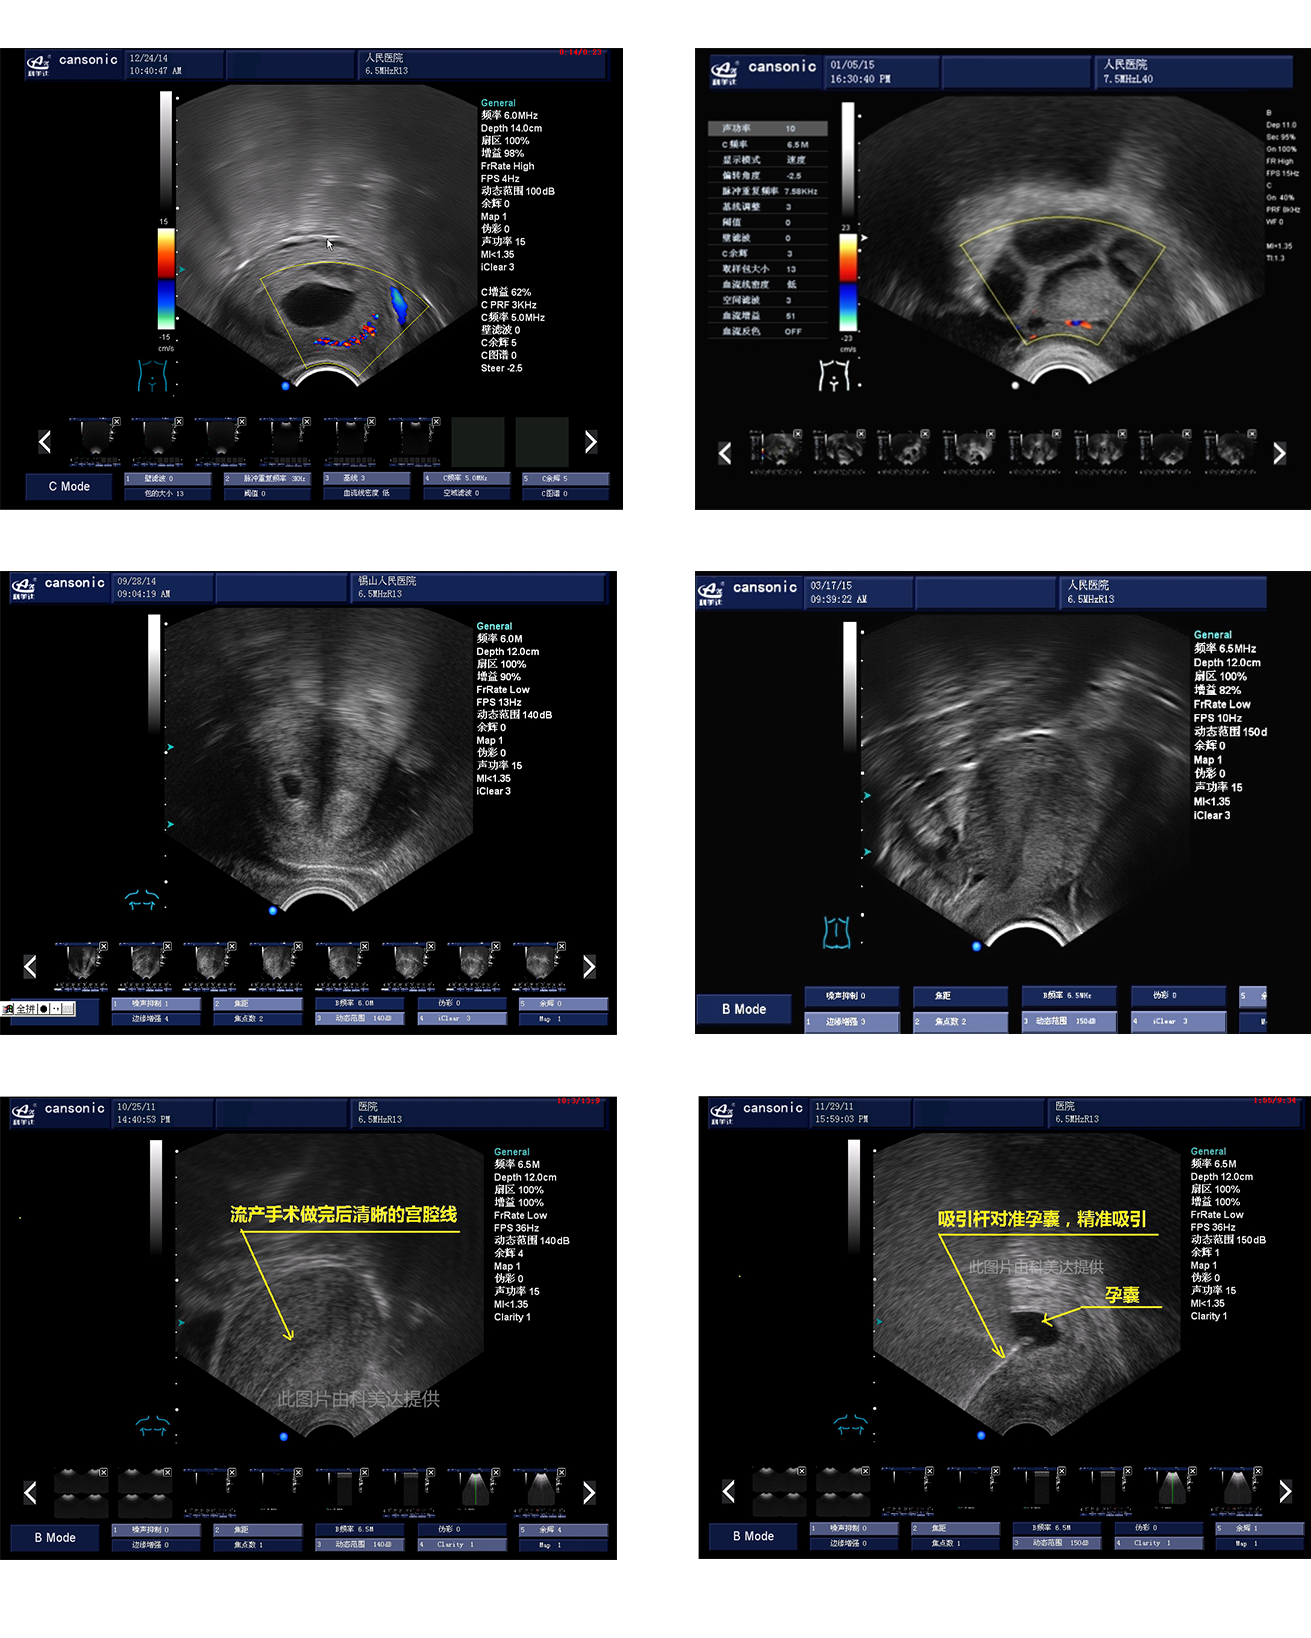

1、融合業(yè)內高端的硬件工藝及智能后處理算法,結合規(guī)范的操作流程,實現(xiàn)對宮腔手術的全程監(jiān)測

2、精準數(shù)字濾波技術,有效降低多普勒噪聲及運動偽像,提升血流及多普勒超聲圖像

4、能量多普勒POWER成像模式彩色多普勒Color成像模式

5、血流靈敏度高,清晰可見

臨床圖示